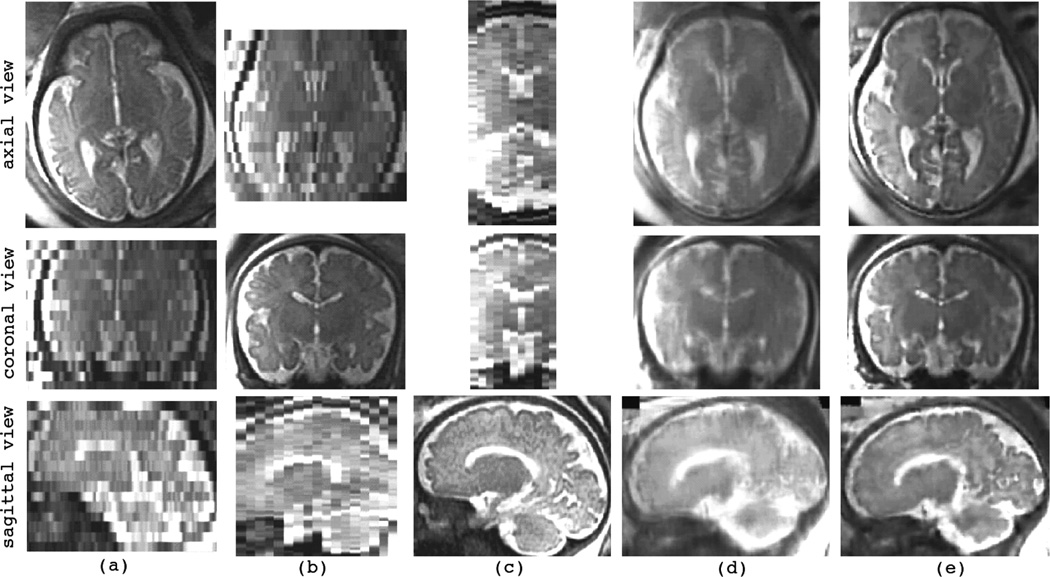

Super Resolution Imaging For Better Medical Image Analysis Median What Is Medical Image Analysis Medical image processing encompasses use and exploration of 3d image datasets of the human body, obtained most commonly from a computed tomography (ct) or magnetic. Machine learning (ml) is an application of ai that can be able to function without being specifically programmed, that learn from data and make predictions or decisions based on past data. Medical image analysis is. What Is Medical Image Analysis.